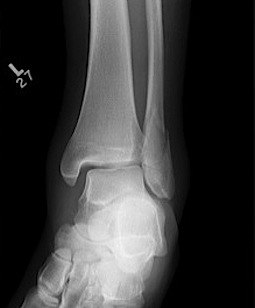

X-ray assessment

3 standard views

AP / Lateral / Mortise

Mortise

- AP with foot internally rotated

- should be symmetrical space around talus

| Increased tibio-fibular clear space | Overlap | Increased medial clear space |

Medial border of the fibula Lateral border of the posterior tibia (incisura fibularis) Measured 1 cm above the plafond |

Overlap of the fibula and the anterior tibial tubercle

Medial talus to lateral medial malleolus |

| <5mm AP and mortise |

> 6 mm AP view > 1 mm mortise view |

< 4mm Equal to superior clear space |

| Syndesmotic injury | Syndesmotic injury |

Deltoid ligament injury Lateral talar shift |

Lateral talar shift / increased medial clear space / deltoid ligament injury

Tibia / fibular overlap < 1mm / syndesmotic injury